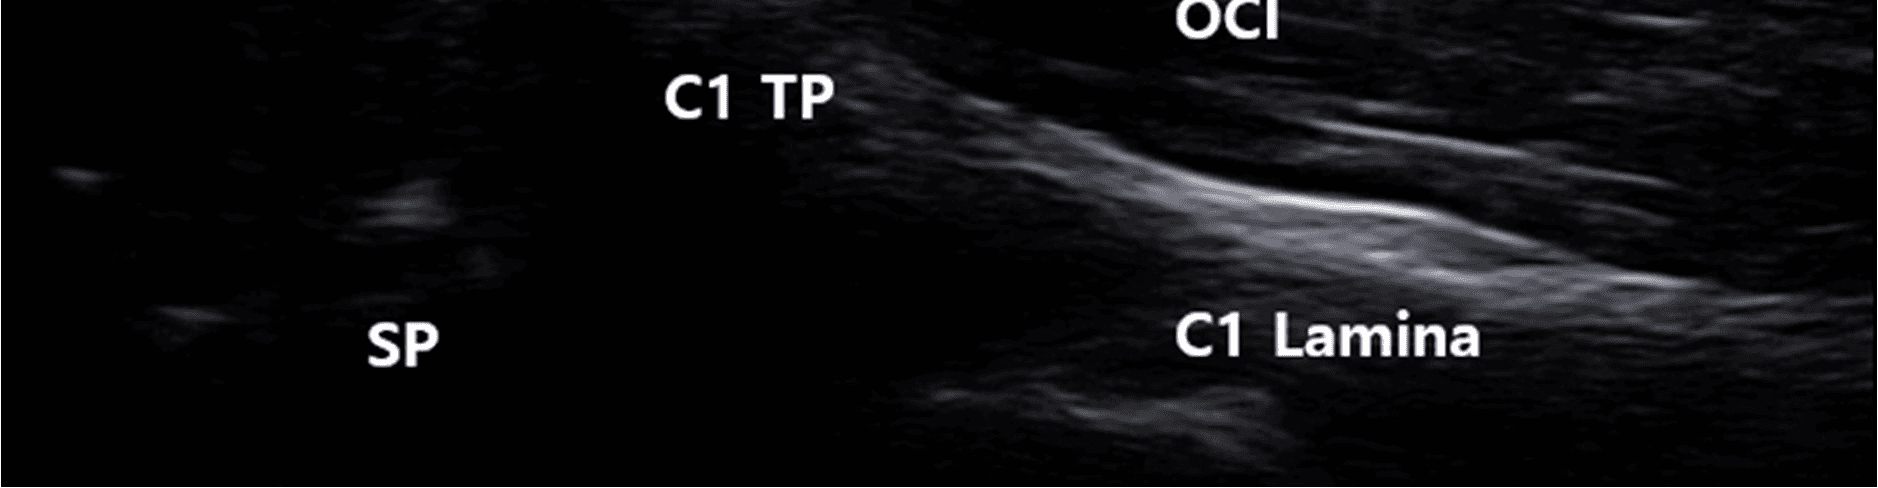

주요 연구 방법으로는 표준화된 프로브 조작 기법을 통해 유양돌기(mastoid process), 경상돌기(styloid process), 이복근 후복부(posterior belly of digastric muscle) 등의 해부학적 표지를 일관되게 시각화하는 것이었습니다. 특히 제1경추(C1)의 횡돌기와 후궁을 기준점으로 활용하여 접근 경로의 재현성을 높였습니다.

특히 고해상도 초음파로 제1경추 횡돌기와 후궁을 안정적으로 시각화할 수 있었고, 프로브를 상방으로 기울이는 heel-toe 기법을 통해 척추동맥을 상부 경추 부위에서 일관되게 확인할 수 있었습니다.